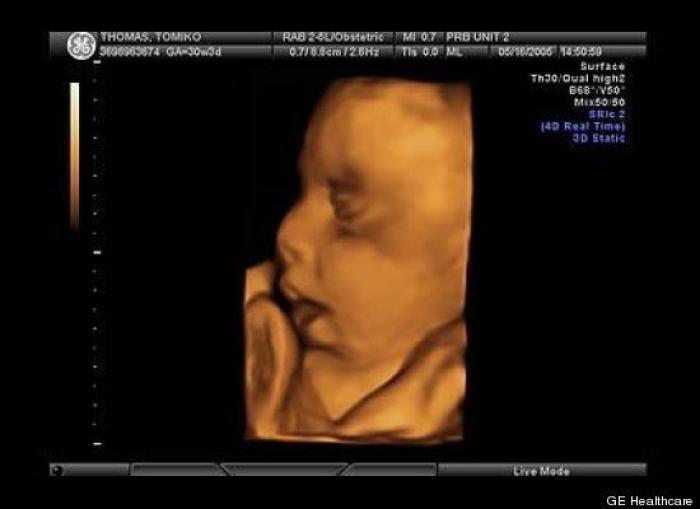

En esta galería puedes ver en fotos como es el desarrollo de un feto de semana en semana:

Desarrollo del feto, en fotos